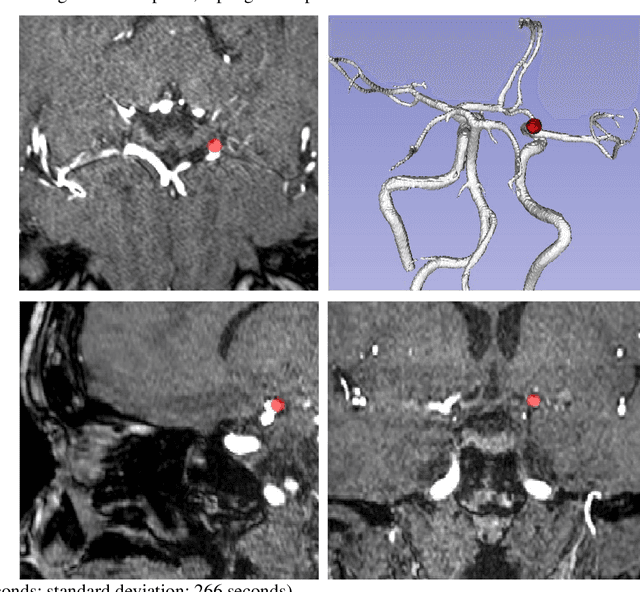

Abstract:Supervised segmentation algorithms yield state-of-the-art results for automated anomaly detection. However, these models require voxel-wise labels which are time-consuming to draw for medical experts. An interesting alternative to voxel-wise annotations is the use of weak labels: these can be coarse or oversized annotations that are less precise, but considerably faster to create. In this work, we address the task of brain aneurysm detection by developing a fully automated, deep neural network that is trained utilizing oversized weak labels. Furthermore, since aneurysms mainly occur in specific anatomical locations, we build our model leveraging the underlying anatomy of the brain vasculature both during training and inference. We apply our model to 250 subjects (120 patients, 130 controls) who underwent Time-Of-Flight Magnetic Resonance Angiography (TOF-MRA) and presented a total of 154 aneurysms. To assess the robustness of the algorithm, we participated in a MICCAI challenge for TOF-MRA data (93 patients, 20 controls, 125 aneurysms) which allowed us to obtain results also for subjects coming from a different institution. Our network achieves an average sensitivity of 77% on our in-house data, with a mean False Positive (FP) rate of 0.72 per patient. Instead, on the challenge data, we attain a sensitivity of 59% with a mean FP rate of 1.18, ranking in 7th/14 position for detection and in 4th/11 for segmentation on the open leaderboard. When computing detection performances with respect to aneurysms' risk of rupture, we found no statistical difference between two risk groups (p = 0.12), although the sensitivity for dangerous aneurysms was higher (78%). Our approach suggests that clinically useful sensitivity can be achieved using weak labels and exploiting prior anatomical knowledge; this expands the feasibility of deep learning studies to hospitals that have limited time and data.